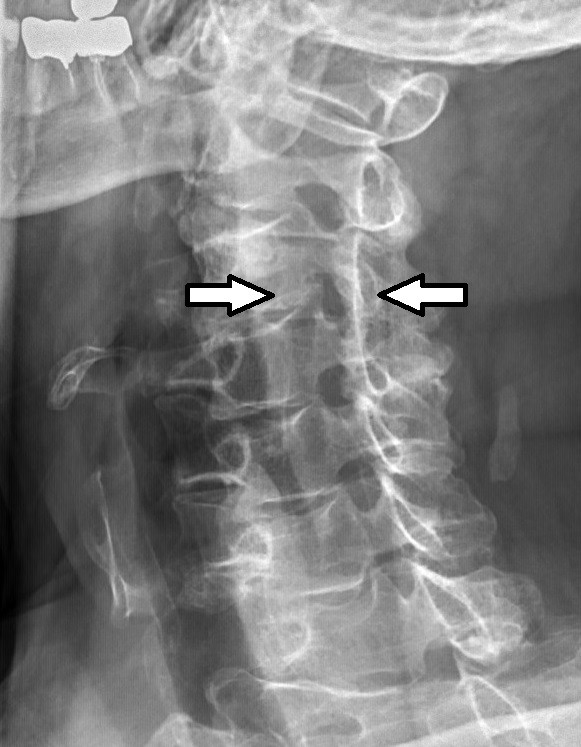

La sténose rachidienne est le processus de rétrécissement des espaces de la colonne vertébrale, le canal par lequel passe la moelle épinière. Cela signifie que, à mesure que ce canal se rétrécit, votre colonne vertébrale subira une pression de tous les côtés. À son tour, cela signifie que vos nerfs ne seront pas en mesure d'envoyer les signaux du cerveau avec précision et à une vitesse régulière aux différentes parties du corps.

Dans l'ensemble, à l'exception des traumatismes et de la croissance tumorale, la principale cause de sténose de la colonne vertébrale est l'usure que notre corps subit. À partir du moment où vous atteignez l'âge de jeune adulte et que vous arrêtez de croître, votre corps réduit sa capacité à produire de nouvelles cellules à un rythme suffisant pour remplacer complètement les anciennes.

Et lorsque le bon type de cellules cesse d'être généré dans les articulations, le corps compense en créant du tissu osseux. Petit à petit, à mesure que nous vieillissons, notre corps devient moins souple et plus sujet à la douleur et à une mobilité réduite.